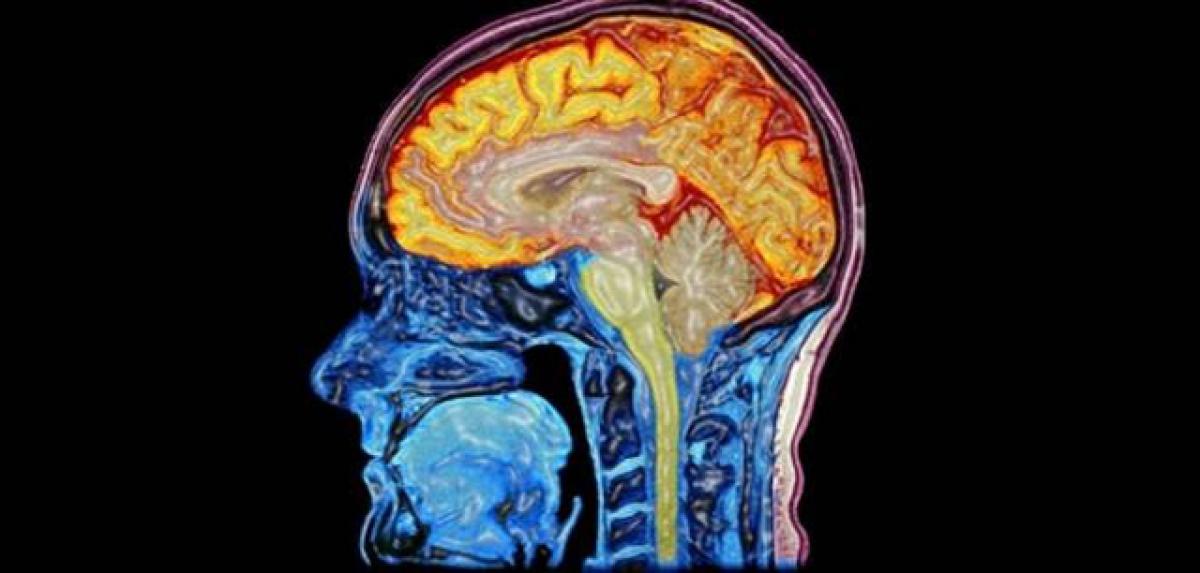

Fat build-up in brain may trigger Alzheimer's disease

Fat build-up in brain may trigger Alzheimer\'s disease. Abnormal build-up of fat in the brain may cause and accelerate the progression of Alzheimer\'s disease, new research has found.

Abnormal build-up of fat in the brain may cause and accelerate the progression of Alzheimer's disease, new research has found. Canadian researchers have discovered accumulations of fat droplets in the brain of patients who died from the disease and have also identified the nature of the fat.